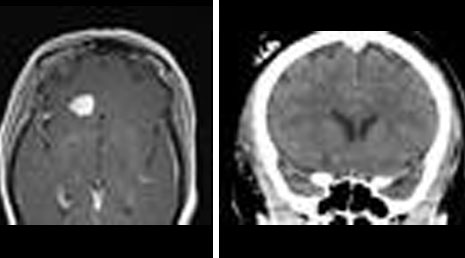

9. Brain abscess - excision